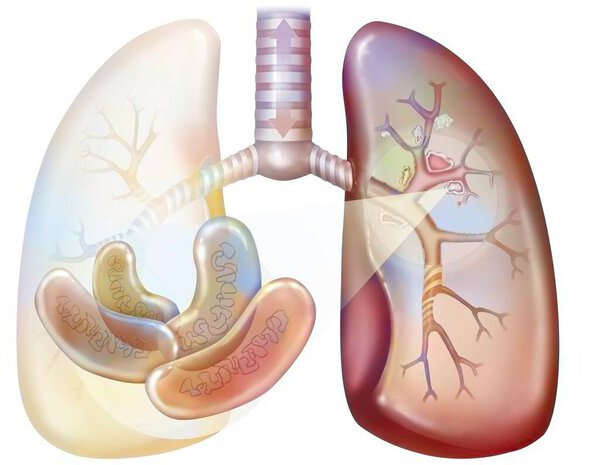

- Рак легких курильщика (с наличием депозитов смолы в бронхах).

Рак легких курильщика (с наличием депозитов смолы в бронхах).

Рак легких курильщика (с наличием депозитов смолы в бронхах).